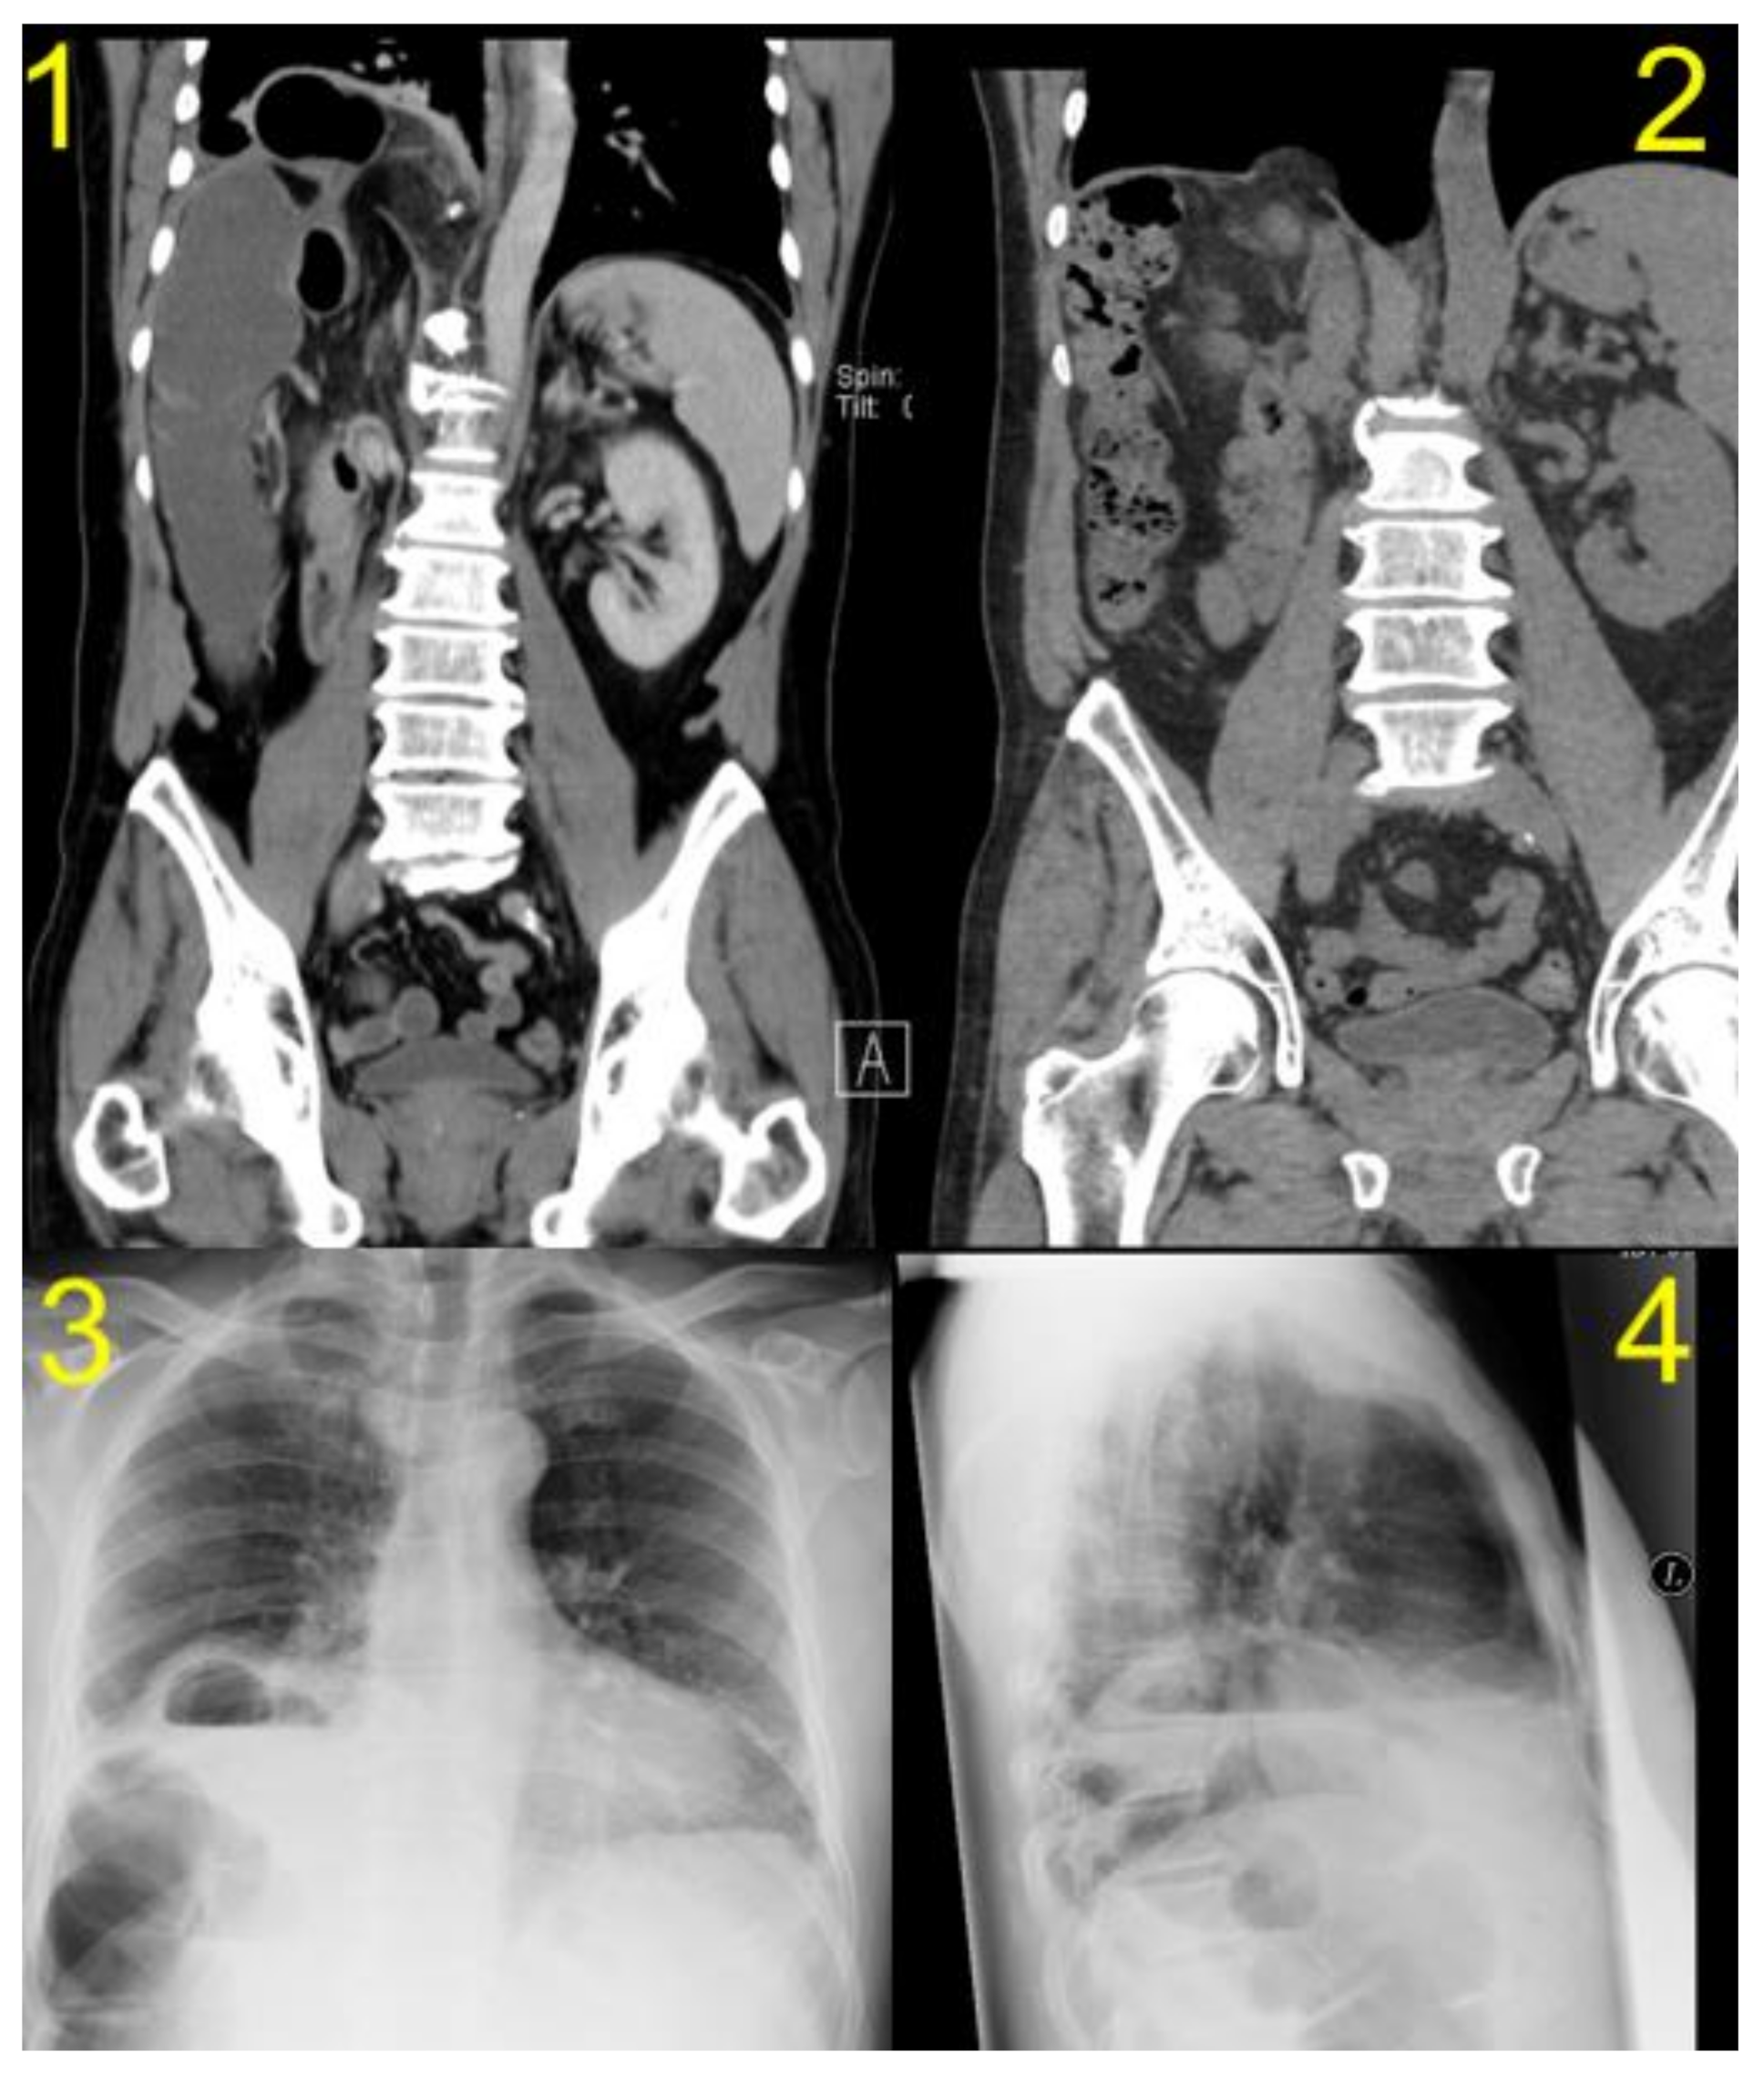

| Diagnostic Study | CT | CT | CT | CT/MRI | CT |

| Herniated organ | right colon flexure, omentum | colon and small bowell | colon and omentum majus | colon | colon |

| Side of hernia | right-sided | right-sided | right-sided | right-sided | right-sided |

| Size of Hernia | 4 cm | <5 cm | 4 cm | 5 cm | 7 cm |